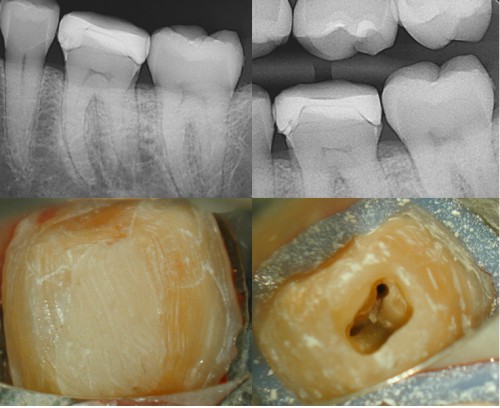

Max 2st Molar Tx thru New Crown

Patient had crown done a few months prior. He developed chewing pain this week. Upon […]